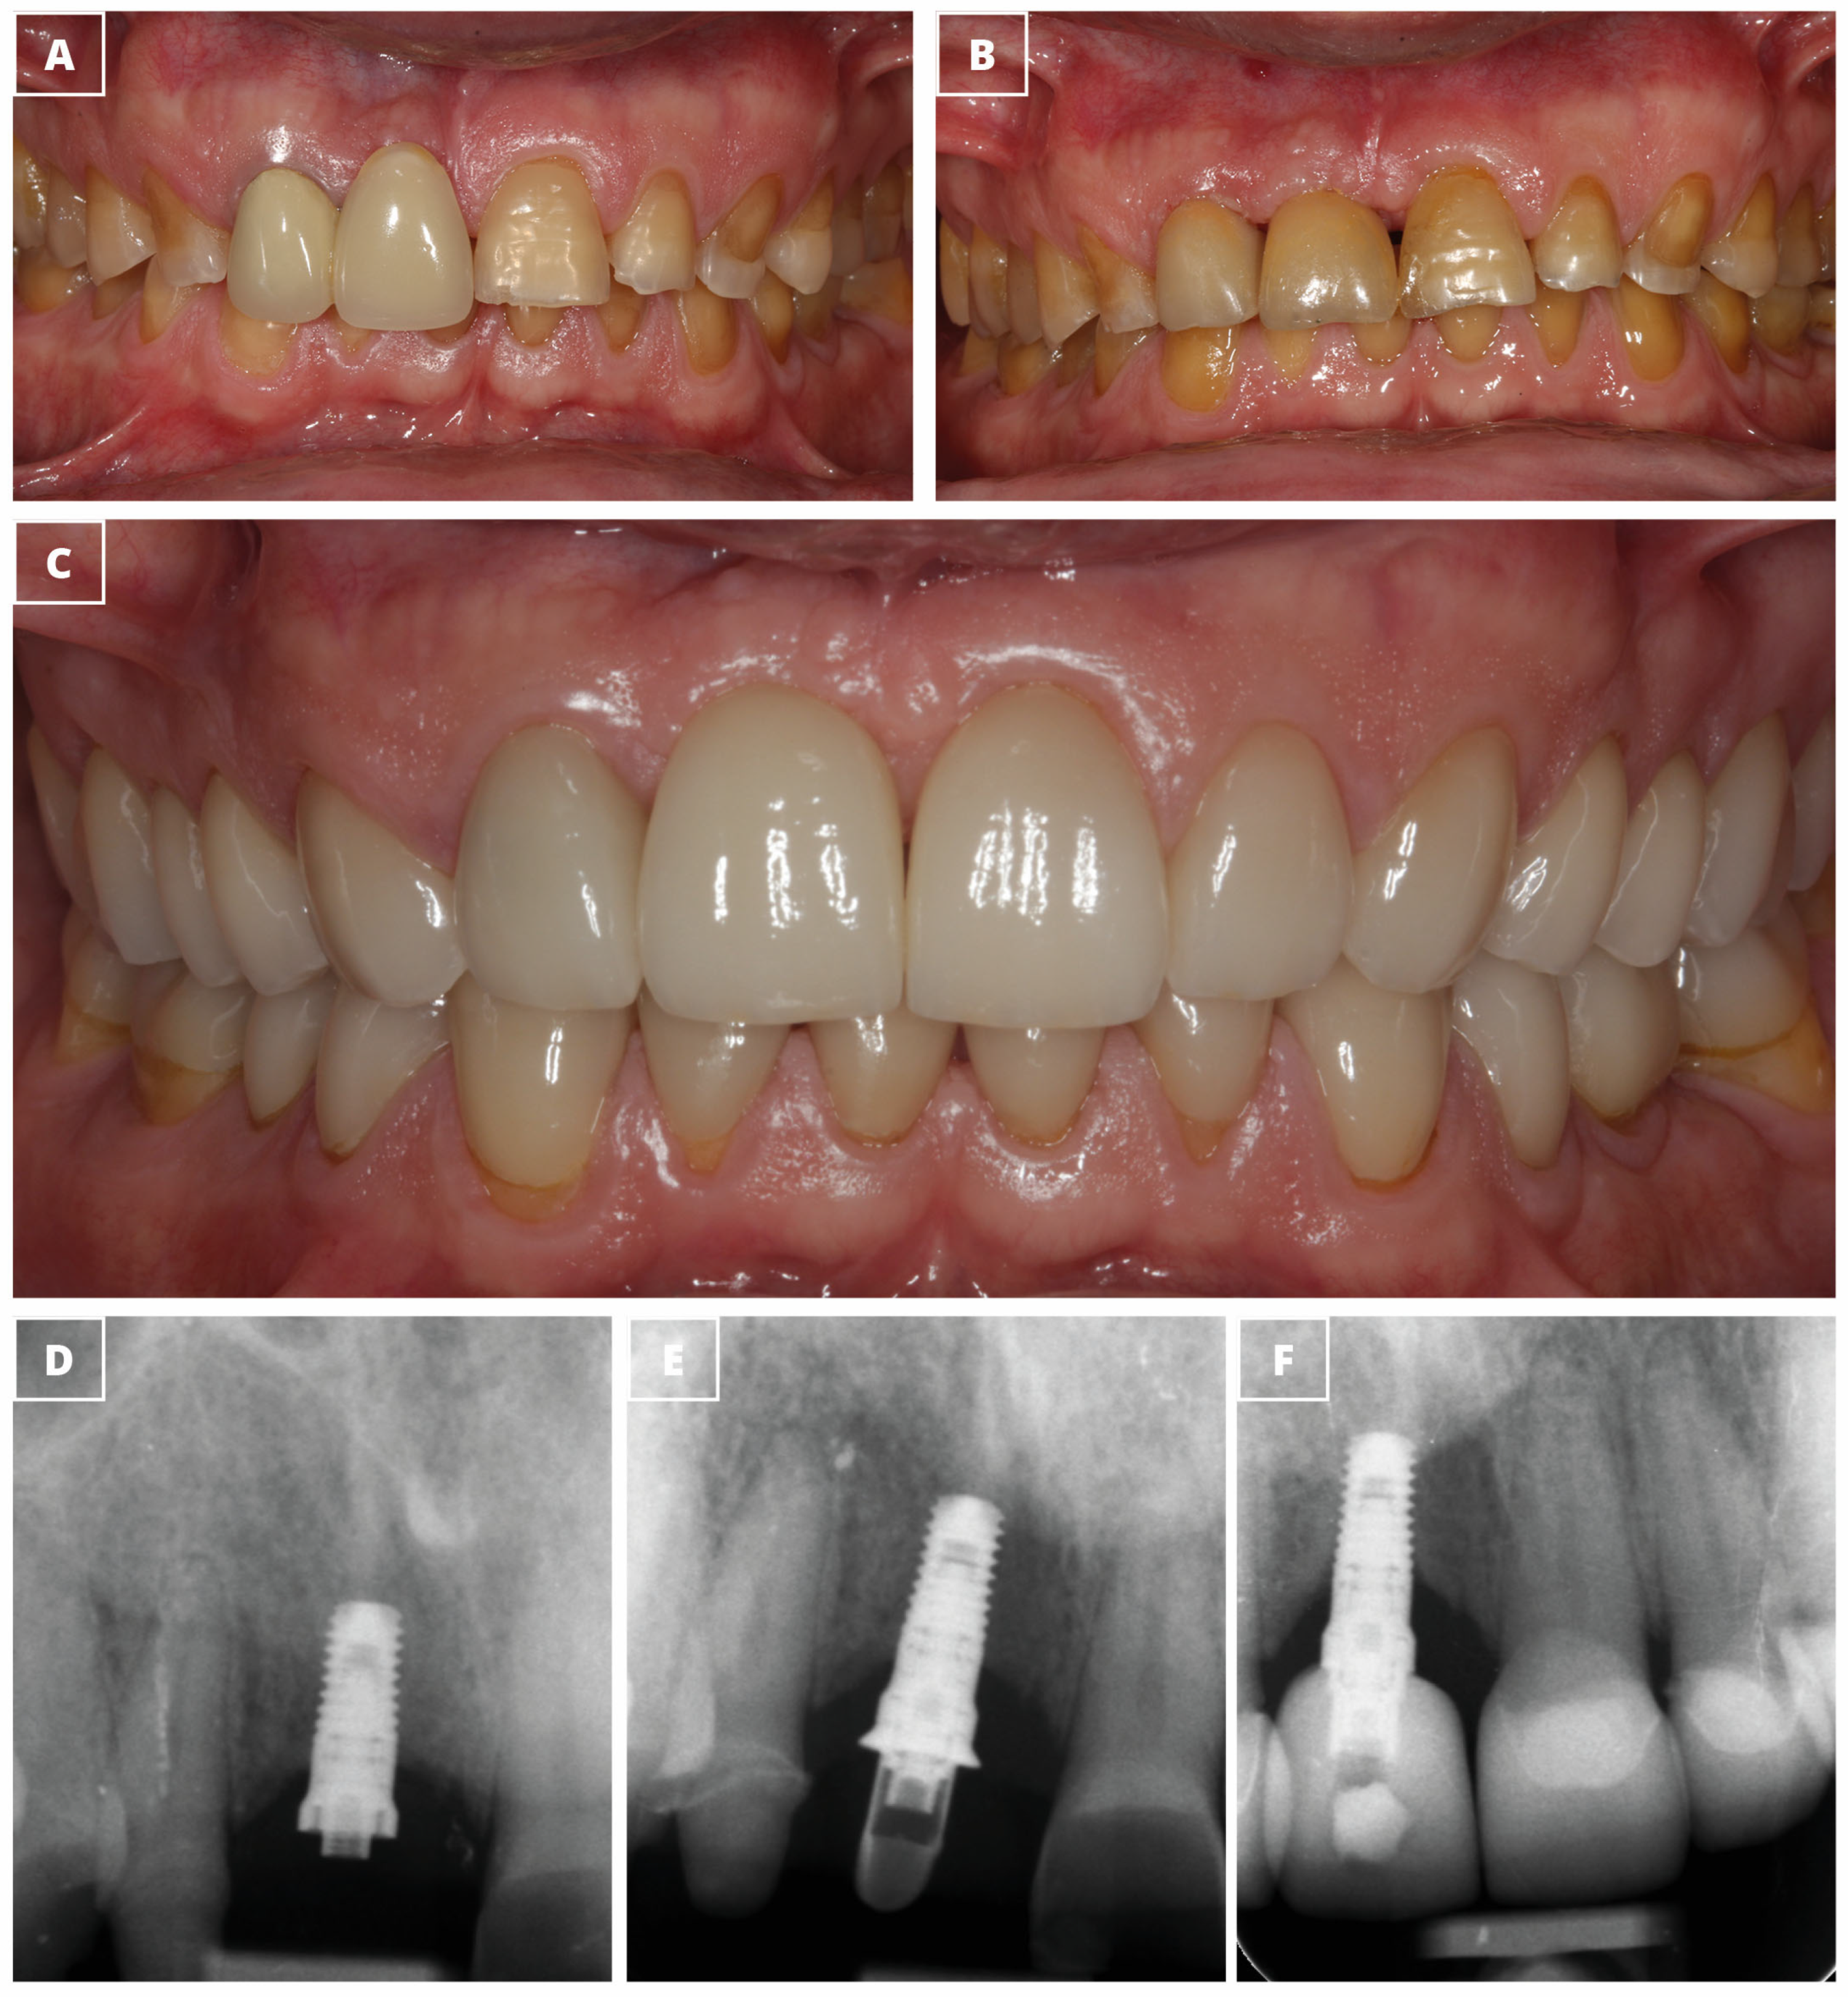

| Pink Esthetic Score | 7.0 ± 2.6 | |

| White Esthetic Score | 7.9 ± 2.0 |